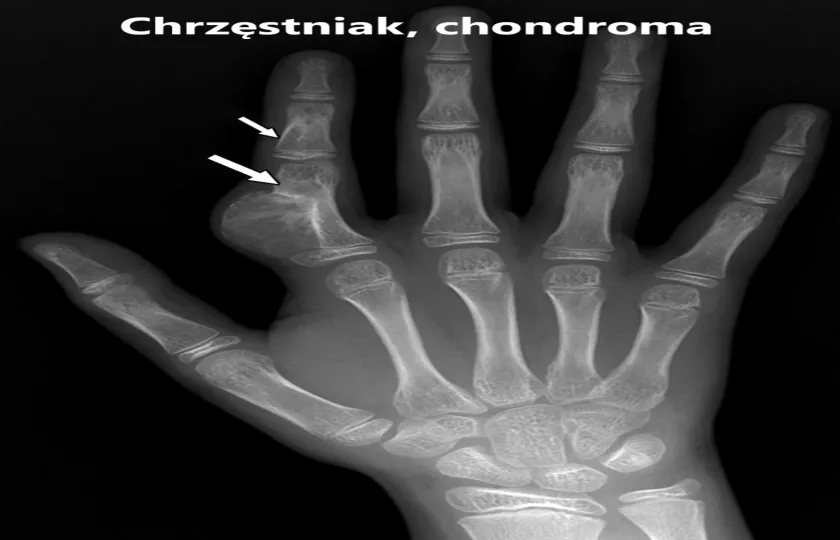

Endochondromy w krótkich kościach rurkowatych (jak dłonie czy stopy) charakteryzują się jednorodnym prześwietleniem, które nierzadko zajmuje całą średnicę kości. Natomiast na zdjęciach długich kości rurkowych chrzęstniaki prezentują się, jako mgliste prześwity o zmiennym kształcie, niekiedy z zaznaczonymi obszarami zwapnień. Na zdjęciach rentgenowskich obraz chrzęstniaka może być podobny do torbieli jednokomórkowej, lokalizowanego ogniska dysplazji włóknistej czy guza olbrzymiokomórkowego. Istotne jest również wykluczenie charakteru złośliwego guza. W celu dokładniejszego ustalenia diagnozy przeprowadza się biopsję, a potem analizuje się materiał pod mikroskopem.